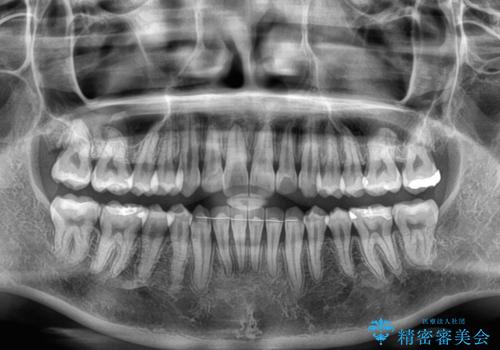

- 上下前歯のデコボコ、特に右上の八重歯を気にして来院された患者様です。

治療後半では悪阻によりマウスピースの装着時間が不十分となることもありましたが、それよりも前にしっかりと装着時間を守って治療を進めることができたため、特に気になるところなく治療を終えることができました。